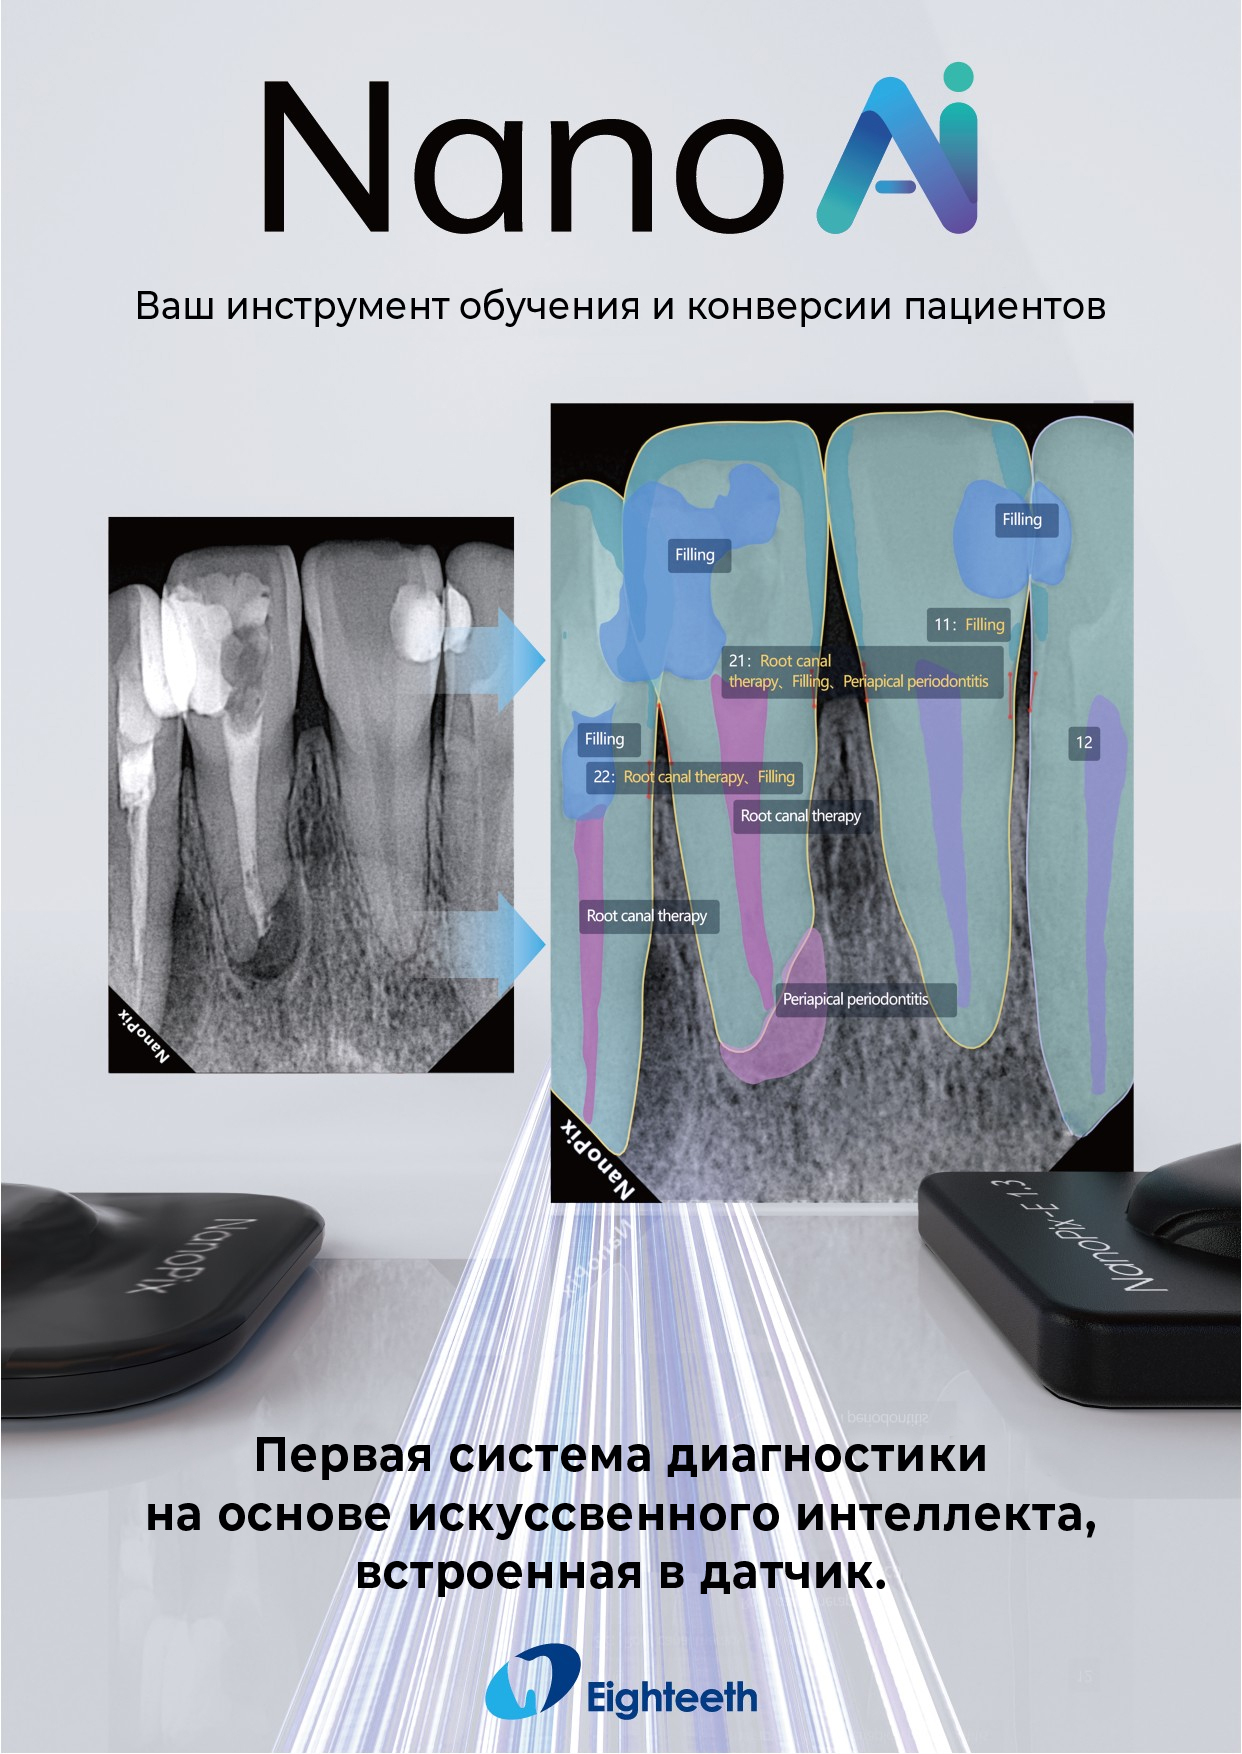

Прибор оснащён высокочувствительным сенсором, с помощью которого устройство фиксирует и передаёт изображение в цифровом виде на компьютер. Принцип работы заключается в следующем: цифровой радиовизиограф размещается в ротовой полости пациента за зубами. С щёчной стороны дентальный рентгеновский аппарат выпускает в направлении радиовизиографа рентгеновские лучи. Лучи, проходя через ткани зуба, фиксируются на радиовизиографе, и полученная информация отображается на экране компьютера. Уникальная технология искусственного интеллекта Nano AI распознаёт зубные патологии, выделяя их цветом и предлагая возможные способы лечения.